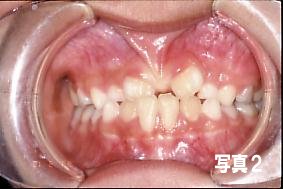

3)明らかに、歯の隙間の原因となっている場合。

(上唇小帯の異常例、写真2)